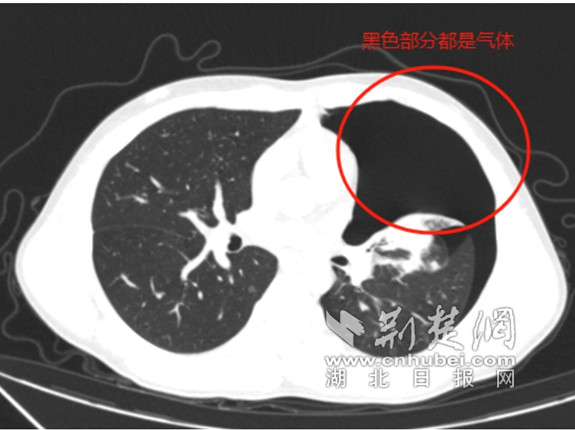

急诊科医生迅速响应,为小江安排了胸部CT检查。结果显示,小江患有“左侧液气胸”,并以“自发性气胸”将他收治到心胸外科继续治疗。心胸外科主任王杰接到值班医师通知,得知患者情况危急,CT影像显示多发肺大疱且气胸已压缩肺组织达50%以上,需立即进行穿刺排气。

CT影像显示气胸已压缩肺组织达50%以上 通讯员供图